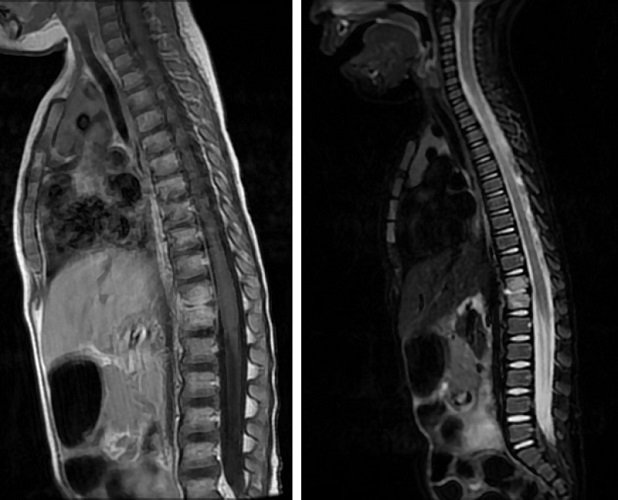

Niña de 2 años consultó por dolor abdominal y cuadro catarral. En días anteriores padeció gastroenteritis autolimitada. Exploración física abdominal y caderas normales. Se pautaron probióticos y reconsultó a los 2 días por persistencia de síntomas, febrícula y rechazo de la deambulación. Ingresó para estudio: analítica sanguínea (reacción en cadena de la polimerasa [PCR] 37,6 mg/l, velocidad de sedimentación globular [VSG] 45 mm), ecografía abdominal (adenitis en fosa iliaca derecha) y radiografía abdominal (colon neumatizado, heces abundantes, sin signos de oclusión). Se pautó desimpactación con laxante y tratamiento con antiinflamatorios durante una semana. Por persistencia de dolor abdominal, reingresó con ampliación de pruebas: analítica sanguínea (PCR <0,5 mg/l), hemocultivo, coprocultivo y Mantoux (negativo), array norovirus positivo en heces. En resonancia magnética (RM), a los 20 días desde inicio del cuadro, se evidencia espondilodiscitis aguda en D11-D12 con afectación del disco (Figura 1), sugiriendo etiología bacteriana, S. aureus por frecuencia, sin descartar Salmonella por contacto con tortuga. Se trató con cloxacilina y cefotaxima intravenosa durante 15 días y posteriormente, cefuroxima oral durante 3 meses con evolución favorable.

Figura 1. Resonancia magnética: espondilodiscitis aguda en D11-D12 con afectación del disco

El diagnóstico suele retrasarse, ya que las radiografías inicialmente son normales. La RM confirma el diagnóstico e informa de la extensión y afectación de partes blandas. En analítica se pueden elevar PCR, VSG y leucocitos. La etiología suele ser bacteriana, pero solo el 30% de las infecciones se confirman con hemocultivos positivos, siendo S. aureus el más frecuentemente aislado (65% de los casos). La localización más frecuente es la lumbar, seguida de la dorsal y la cervical.